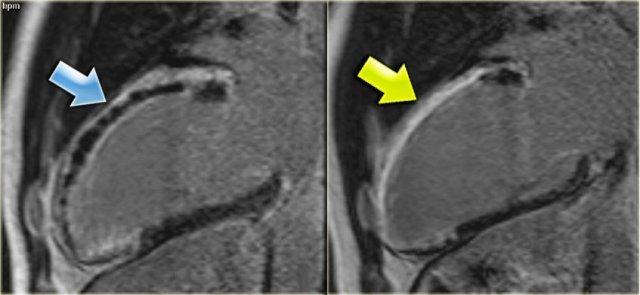

Bên trái là ảnh cine trục dài 6 ngày sau tái thông mạch trong nhồi máu cấp thành dưới.

Hãy xem video trước rồi tiếp tục đọc.

- Thành trước co bóp tốt

- Mặc dù đã được tái thông mạch, thành dưới vẫn còn giảm vận động.

Tiếp tục xem ảnh ngấm thuốc muộn.

Bên trái là ảnh ngấm thuốc muộn trục dài của cùng bệnh nhân.

Mức độ ngấm thuốc của cơ tim dưới 50%.

Đây là dấu hiệu tiên lượng tốt và có thể kỳ vọng sự phục hồi một phần chức năng co bóp.

Tiếp tục xem ảnh cine bốn tháng sau.

Bên trái là hình ảnh của cùng bệnh nhân bốn tháng sau nhồi máu thành dưới và tái thông mạch.

Ảnh cine trục dài cho thấy chức năng thành dưới đã cải thiện.

Từ đó có thể kết luận rằng tình trạng giảm vận động là do choáng cơ tim.

Các vùng cơ tim không có hoặc có rất ít bằng chứng tăng ngấm thuốc (tức là nhồi máu) có khả năng cao phục hồi chức năng, trong khi các vùng tăng ngấm thuốc xuyên thành gần như không có khả năng phục hồi.